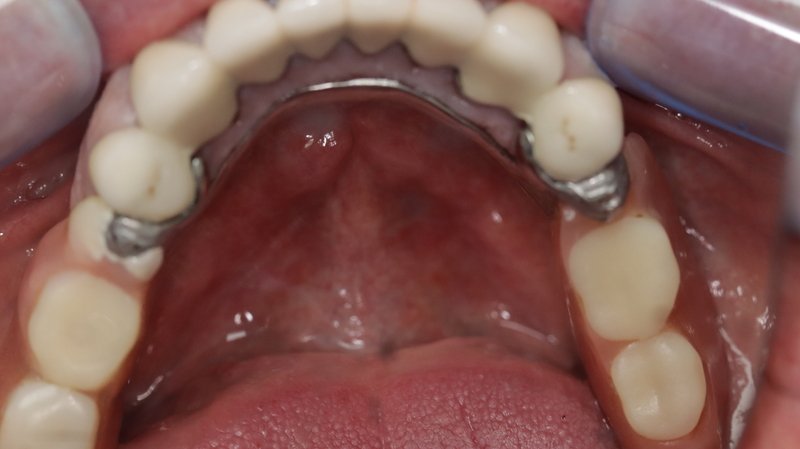

Replacement of old upper bar retained Chrome denture with fixed upper prosthesis.